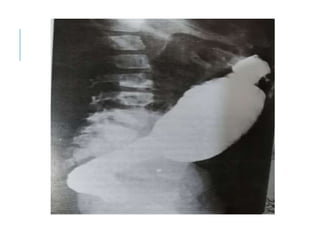

Inability to pass NG or OG tube .

Plain x-ray shows coiled feeding tube, air distended

stomach(coexisting TEF), airless scaphoid

abdomen(isolated EA).

Esophagogram with contrast medium demonstrate the

defect (isolated TEF).

Endoscopy and Bronchoscopy.